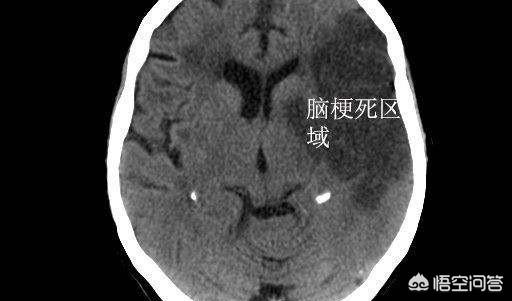

(特に濃い色が梗塞部分)

海綿状脳梗塞のように、比較的若い年齢で脳梗塞を起こしても症状がない場合もあり、せいぜいめまい程度ですむ人が多いが、比較的高齢で脳梗塞を起こすと、50パーセント以上の確率で、そのような患者が助かることは非常に難しい;